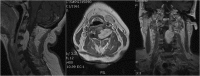

We report a case of a giant intra and extradural cervical schwannoma in a patient affected by a severe myelo-radiculopathy. Clinical features, diagnosis and the issues concerning the surgical management of this benign tumor are discussed. We also review similar cases previously reported in the literature. A 50-year old caucasian woman was complaining of a 1 year of neck pain and worsening motor impairment in all four limbs causing the inability to walk. Neuroradiological assessment revealed a suspected schwannoma involving the nerve roots from C3 to C5, compressing and deviating the spinal cord. The vertebral artery was also encased within the lesion, but still patent. A posterior cervical laminectomy with a microsurgical extradural resection of the lesion was performed. Moreover, an accurate dissection of the lesion from the vertebral artery and the resection of the intraspinal component was achieved. Vertebral fixation with screws on the lateral masses of C3, C5 and C6 and a hook on C1 was performed. The procedure was secured using electroneurophysiological monitoring. A progressive improvement of the motor functions was achieved. A cervical post-contrast MRI revealed optimal medullary decompression and a gross-total resection of the lesion. Schwannomas are benign, slowly growing lesions which may cause serious neurological deficit. Early diagnosis is necessary and it maybe aided by imaging studies such as MRI or CT. The accepted treatment for these tumors is surgical resection and, when indicated, vertebral fixation.